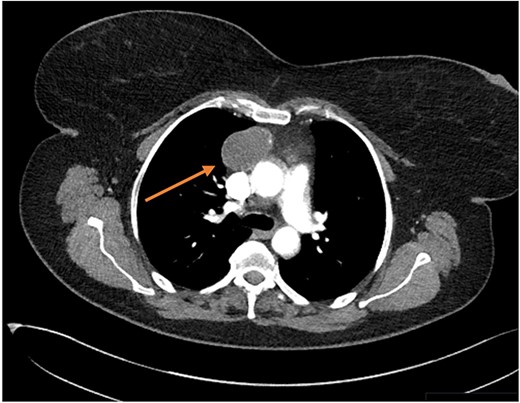

Three months later the patient re-presented with intermittent chest pain associated with a 2-day history of non-productive cough. She was investigated with a chest X-ray and then a contrast CT chest (Figs 1 and 2). Contrast CT chest demonstrated a 20 mm × 40 mm large, slightly lobulated, oval-shaped right anterior mediastinal mass placed more in the superior mediastinum (Fig. 2). The appearance suggested a cystic density within the patchy calcification in the capsule wall. The multidisciplinary team concluded the mass was a thymic or pericardial cyst and planned for surgical excision if there was any progression of the mass.